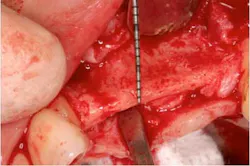

Fig. 7